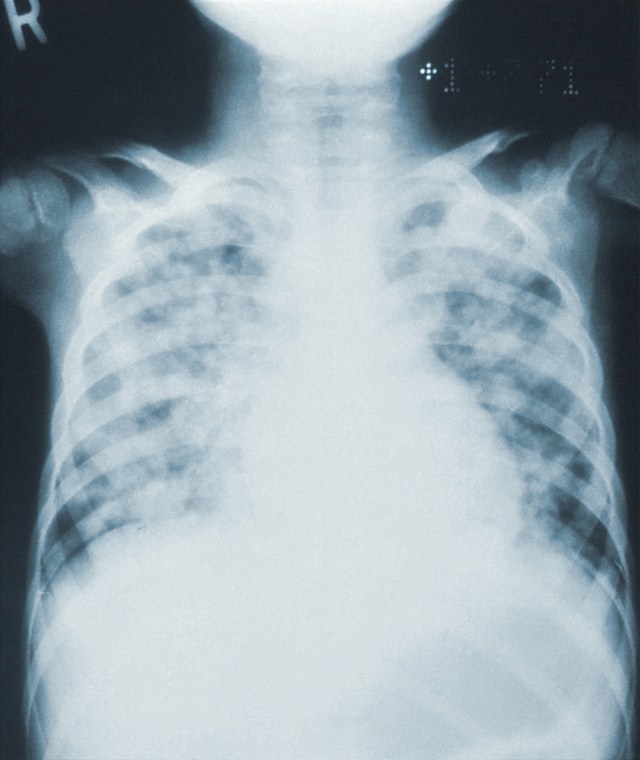

Stage IV adult lymphoma; drawing shows four panels: (a) the top left panel shows cancer in the liver; (b) the top right panel shows cancer in the left lung and in two groups of lymph nodes below the diaphragm; (c) the bottom left panel shows cancer in the left lung and in a group of lymph nodes above the diaphragm and below the diaphragm; and (d) the bottom right panel shows cancer in both lungs, the liver, and the bone marrow. Also shown is primary cancer in the lymph nodes and a pullout of the brain with cerebrospinal fluid.